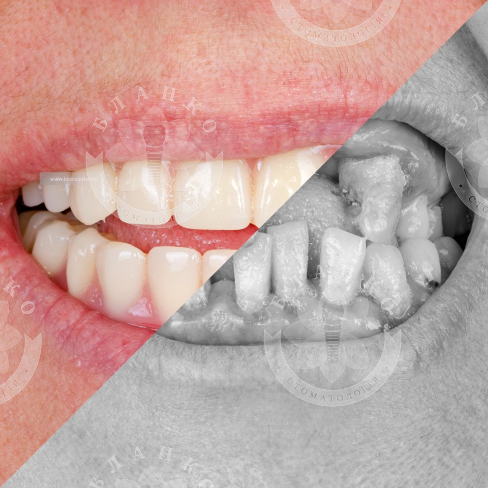

🧐🆘 Пациент обратился со следующей проблемой: генерализованный пародонтит на верхней и нижней челюсти, подвижность зубов, утрата костной ткани.

👨⚕️После полного прохождения лечения — установлены импланты на верхней и нижней челюсти, зафиксированы две несъемные ортопедические конструкции на верхнюю и нижнюю челюсть.

💎 Человек реабилитирован, Стоматология «Бланко» вернула возможность полноценно кушать, улыбаться и наслаждаться жизнью!